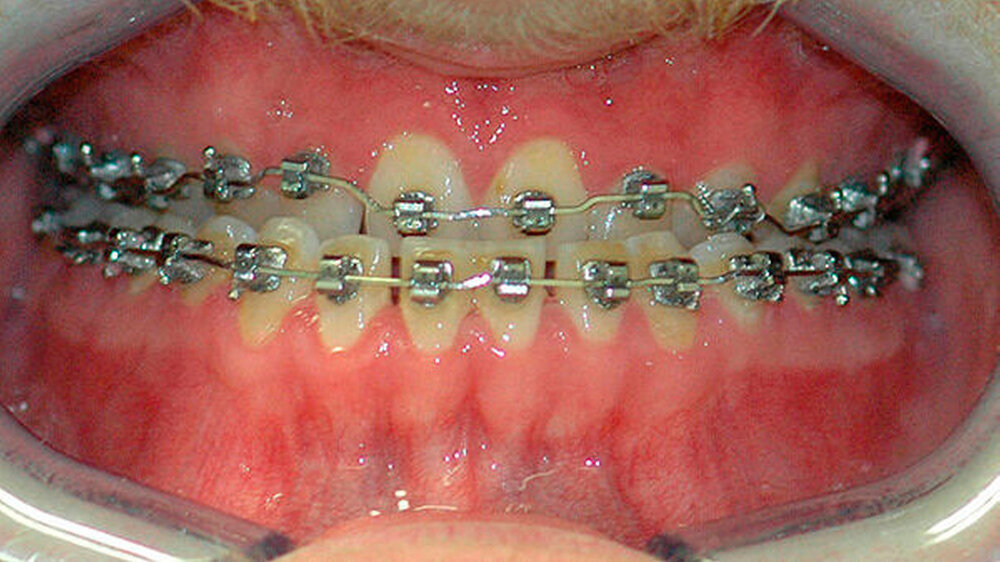

Die Abbildungen 1 und 2 zeigen die klinische Situation bei Erstvorstellung: Der Unterkiefer ist zu prominent. Der Oberkiefer und das Mittelgesicht liegen zurück. In der Front liegt ein umgekehrter Überbiss vor. Der Unterkiefer steht vor dem Oberkiefer. Das erschwert das Abbeißen und Kauen der Nahrung. Die Scans (siehe Abbildungen) dokumentieren, wie aufwendig die virtuelle Operationsplanung erfolgen musste.